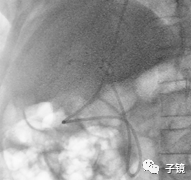

第一次插管进了胰管方向。

取石球囊怎么取石“ERCP球囊取石细节讨论”学习笔记_https://www.jmylbn.com_新闻资讯_第4张

第二次进了胆管,造影发现胆总管中段和下段均有多发结石负影。

取石球囊怎么取石“ERCP球囊取石细节讨论”学习笔记_https://www.jmylbn.com_新闻资讯_第5张